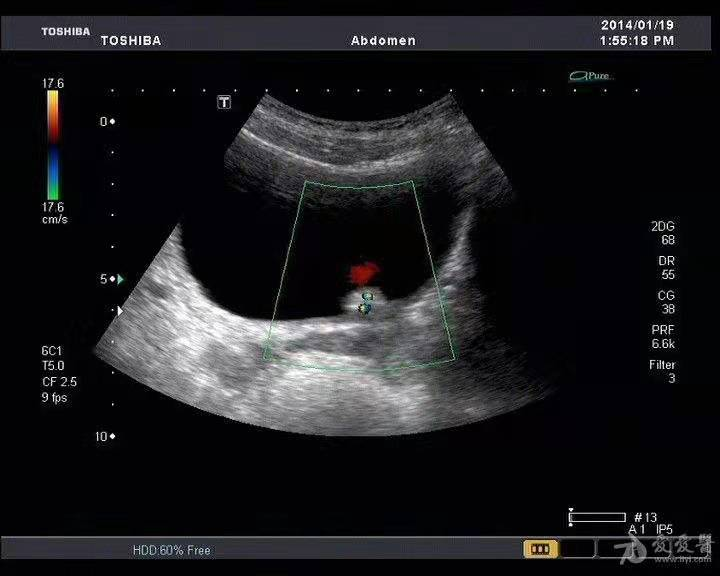

临床上遇到无痛性血尿,我们会怎么做呢?首先我们会通过彩超进行初步筛查,了解一下膀胱里有没有长肿瘤。

彩超结果往往是这样的↓

通过彩超我们可以看到膀胱里有一个小结节,但是结节的具体性质彩超还是无法确定。那有人会说了,能不能做个CT呀,CT不是更清楚吗?